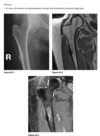

4

23 year old man with pain in the right hip

An anteroposterior view of the pelvis

shows flaring of the metaphyseal regions of

the proximal femurs and numerous osteochondromas

arising from the right iliac crest, pubic bones, and proximal right femur (arrows).

Axial CT through upper pelvis - Large right exostosis with soft tissue mass.

AP radiograph of knee - multiple osteochondromas arising from femur and fibula.

DIAGNOSIS: Multiple hereditary exostosis

AD disorder age 10-20s

Signs of malignant transformation - Growth of previous stable exostosis, new or increasing calcifications, new bony erosion

Associated with chondrosarcoma